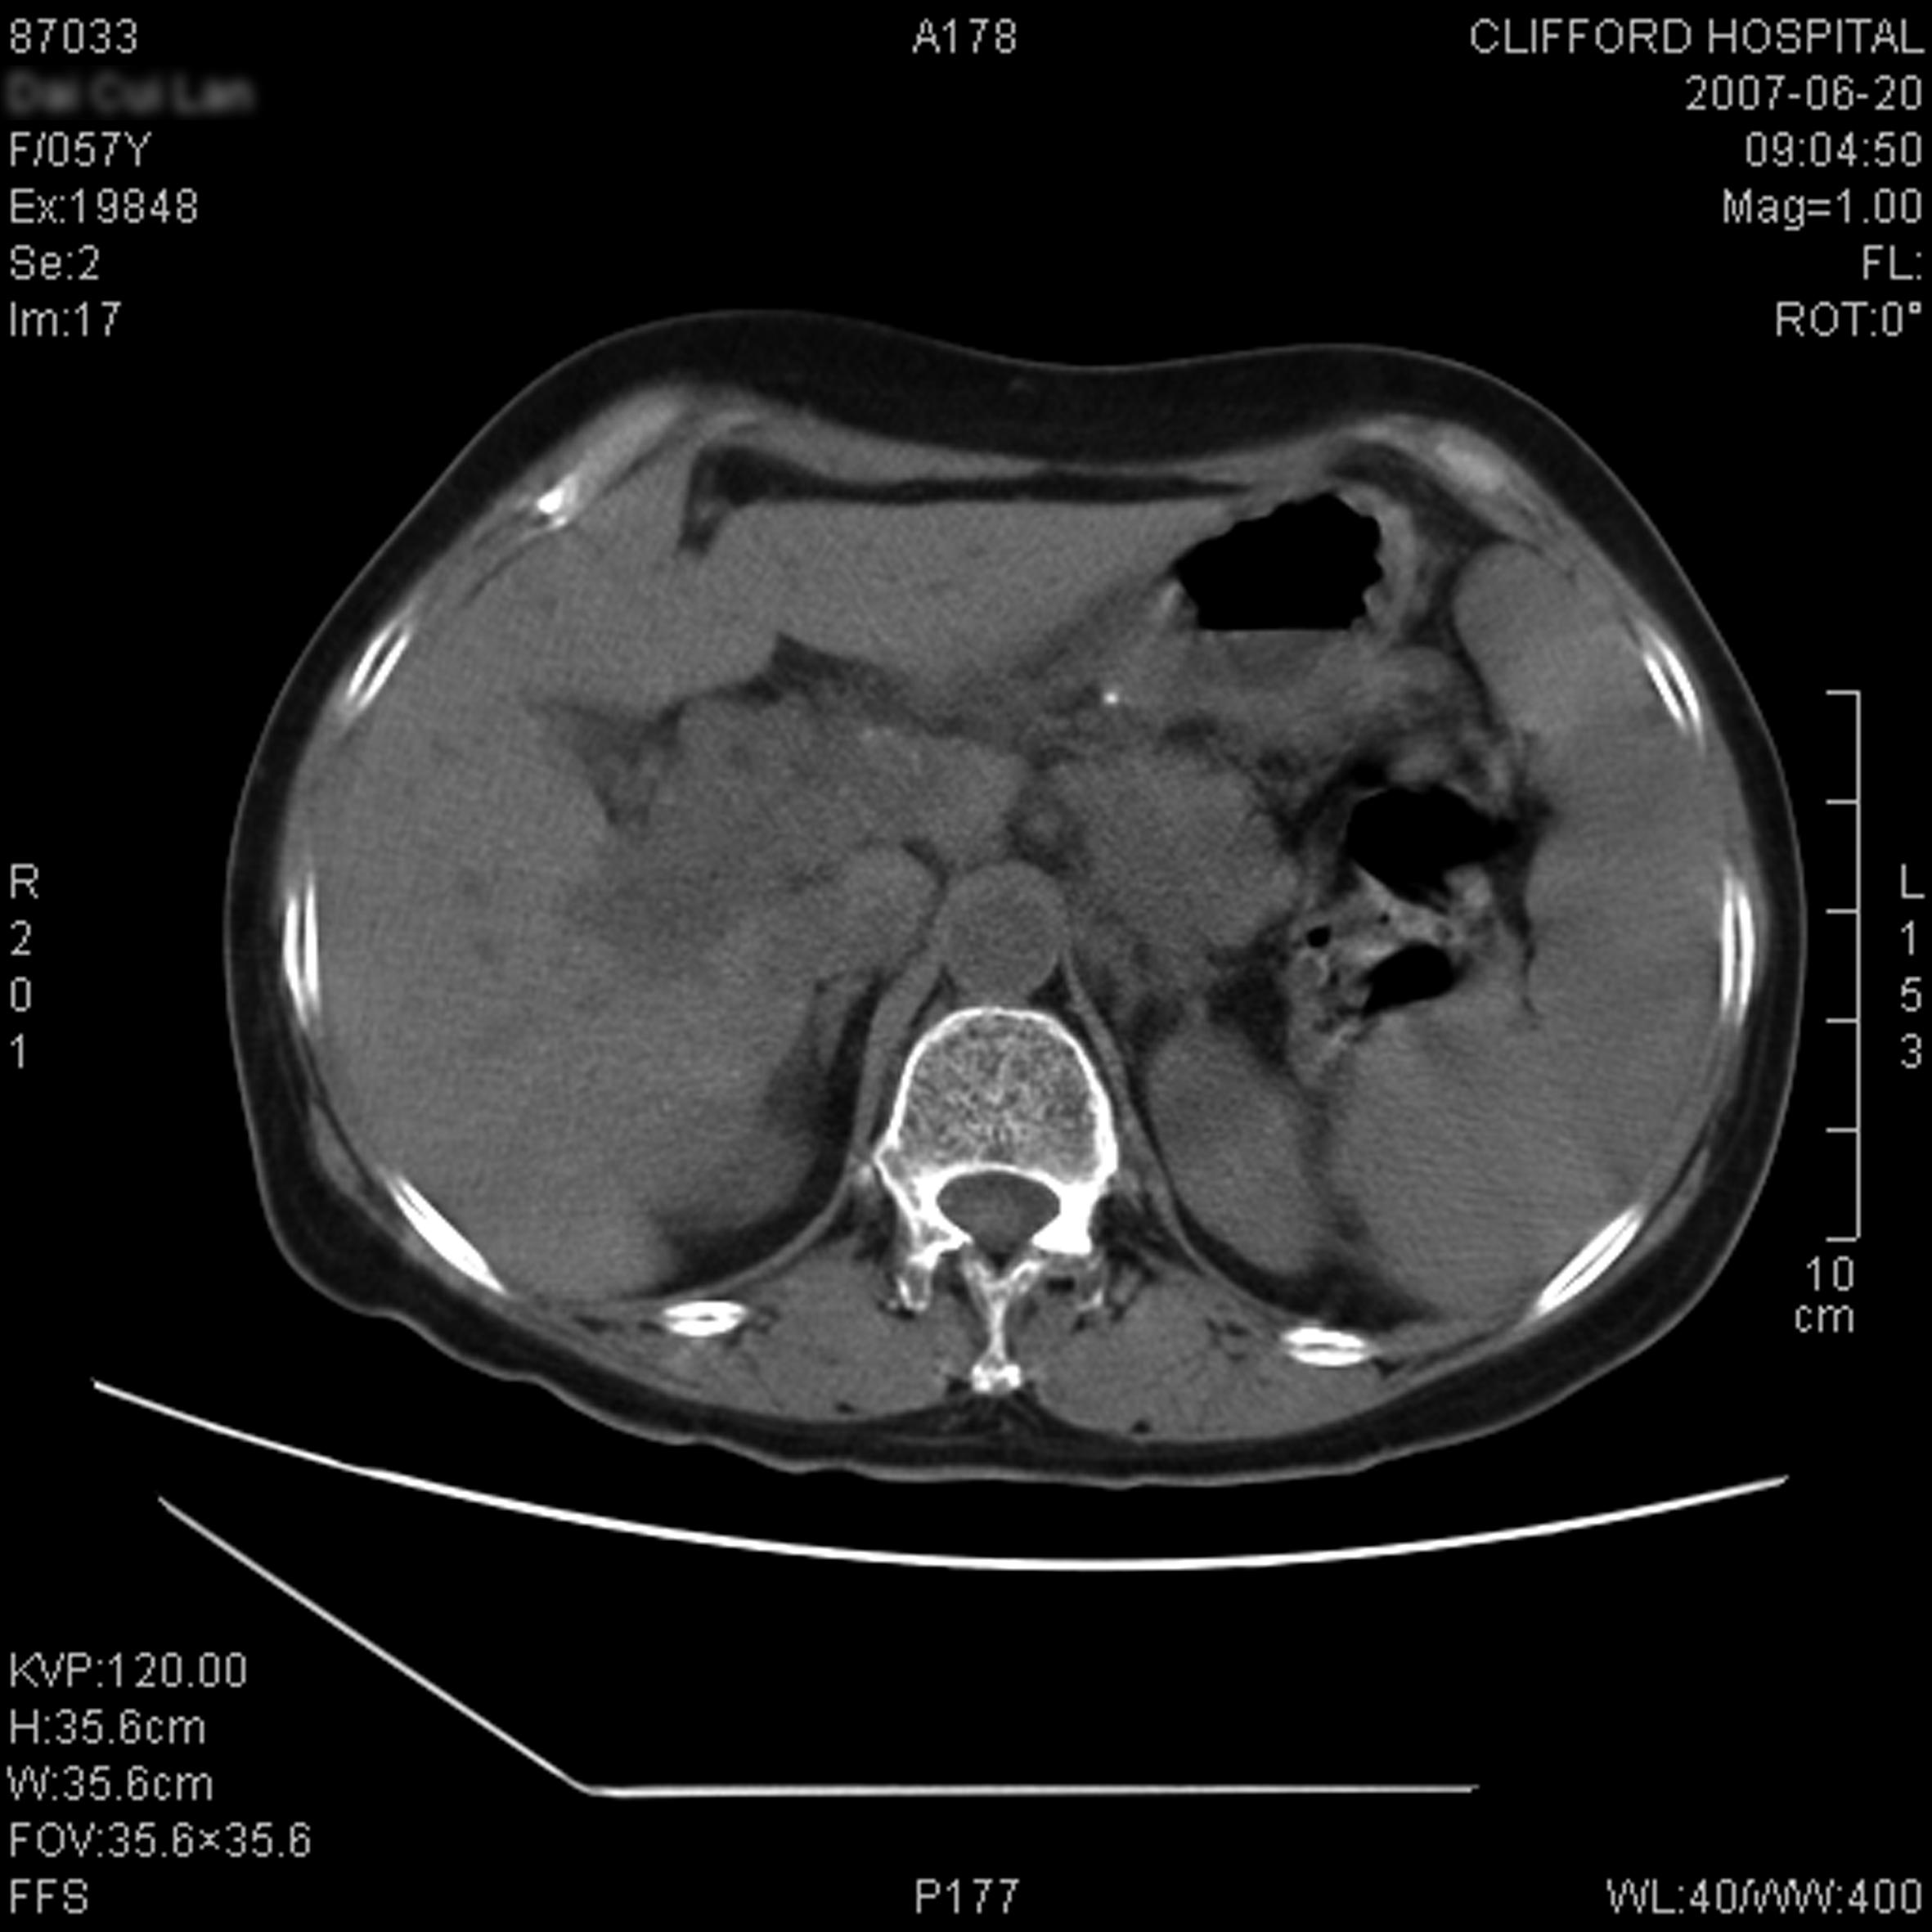

Stomach cancer CT – wikidoc

Typical Cases / Gastric Cancer__Clifford Hospital

Typical Cases / Gastric Cancer__Clifford Hospital